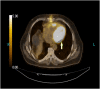

Case presentation: We present a case of primary cardiac sarcoma. Our patient was presented in the department of emergency medicine (ED) in our institute with shortness of breath on exertion associated with orthopnea. Based on the history and cardiovascular examination, he underwent an echocardiogram, which revealed a sizeable echogenic density in the right ventricular outflow tract. He underwent surgical resection of the cardiac mass via median sternotomy and total cardiopulmonary bypass approach. The patient was eventually diagnosed with primary cardiac sarcoma, confirmed by tissue biopsy after surgical intervention.